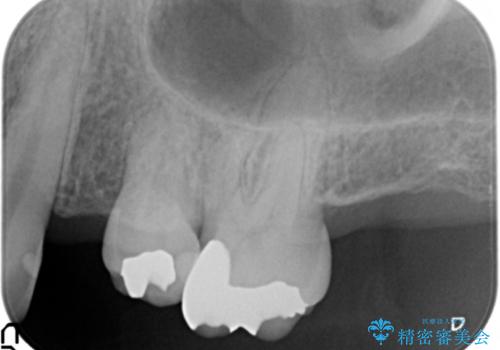

インプラント治療を行うには隙間が狭すぎるためブリッジか入れ歯をご提案したところ、取り外しの必要な入れ歯は希望されずブリッジを用いて機能・審美性の改善を行っていくこととなりました。

ブリッジの長期的な予後のためには支台となる歯の位置・清掃性が重要となりますが、今回ブリッジを製作するにあたり位置の悪い左上小臼歯を補綴前小矯正を行い位置を改善します。